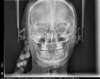

Traitement par gouttières et chirurgie

Etapes intermédiaires